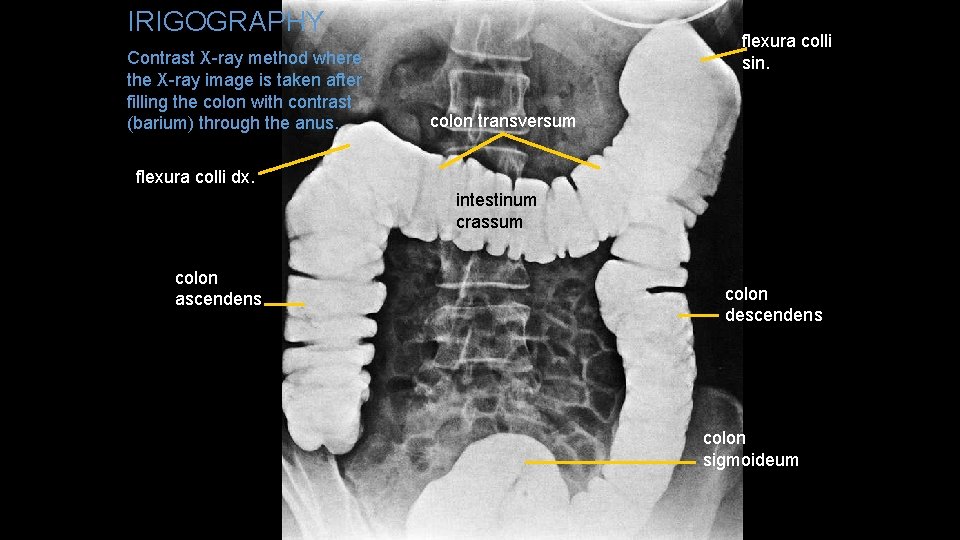

IRIGOGRAPHY Contrast X-ray method where the X-ray image is taken after filling the colon with contrast (barium) through the anus. flexura colli sin. colon transversum flexura colli dx. intestinum crassum colon ascendens colon descendens colon sigmoideum